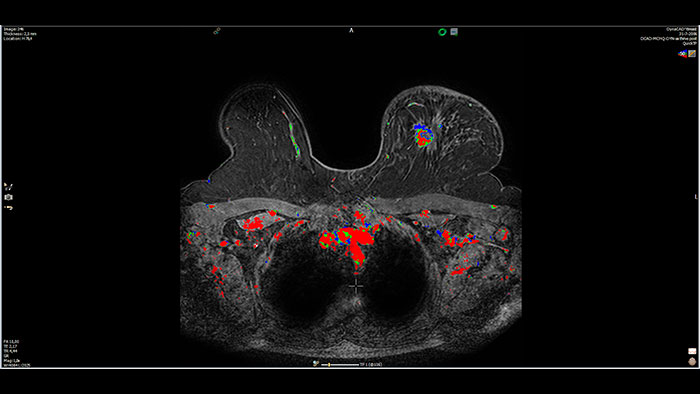

Next generation of breast care

Tailored to enhance the review and analysis of MRI breast studies by providing a flexible workspace with custom hanging protocols and multi-vendor** viewing capabilities. DynaCAD’s automatic segmentation allows on-the-fly user modification and provides volume analysis, lesion composition statistics, histograms, and a 3D rendered morphological overview.

Lesion characterization by reviewing vascular leakage

Designed to visualize T1 weighted DCE 3D datasets and assist in analyzing the tissue response.